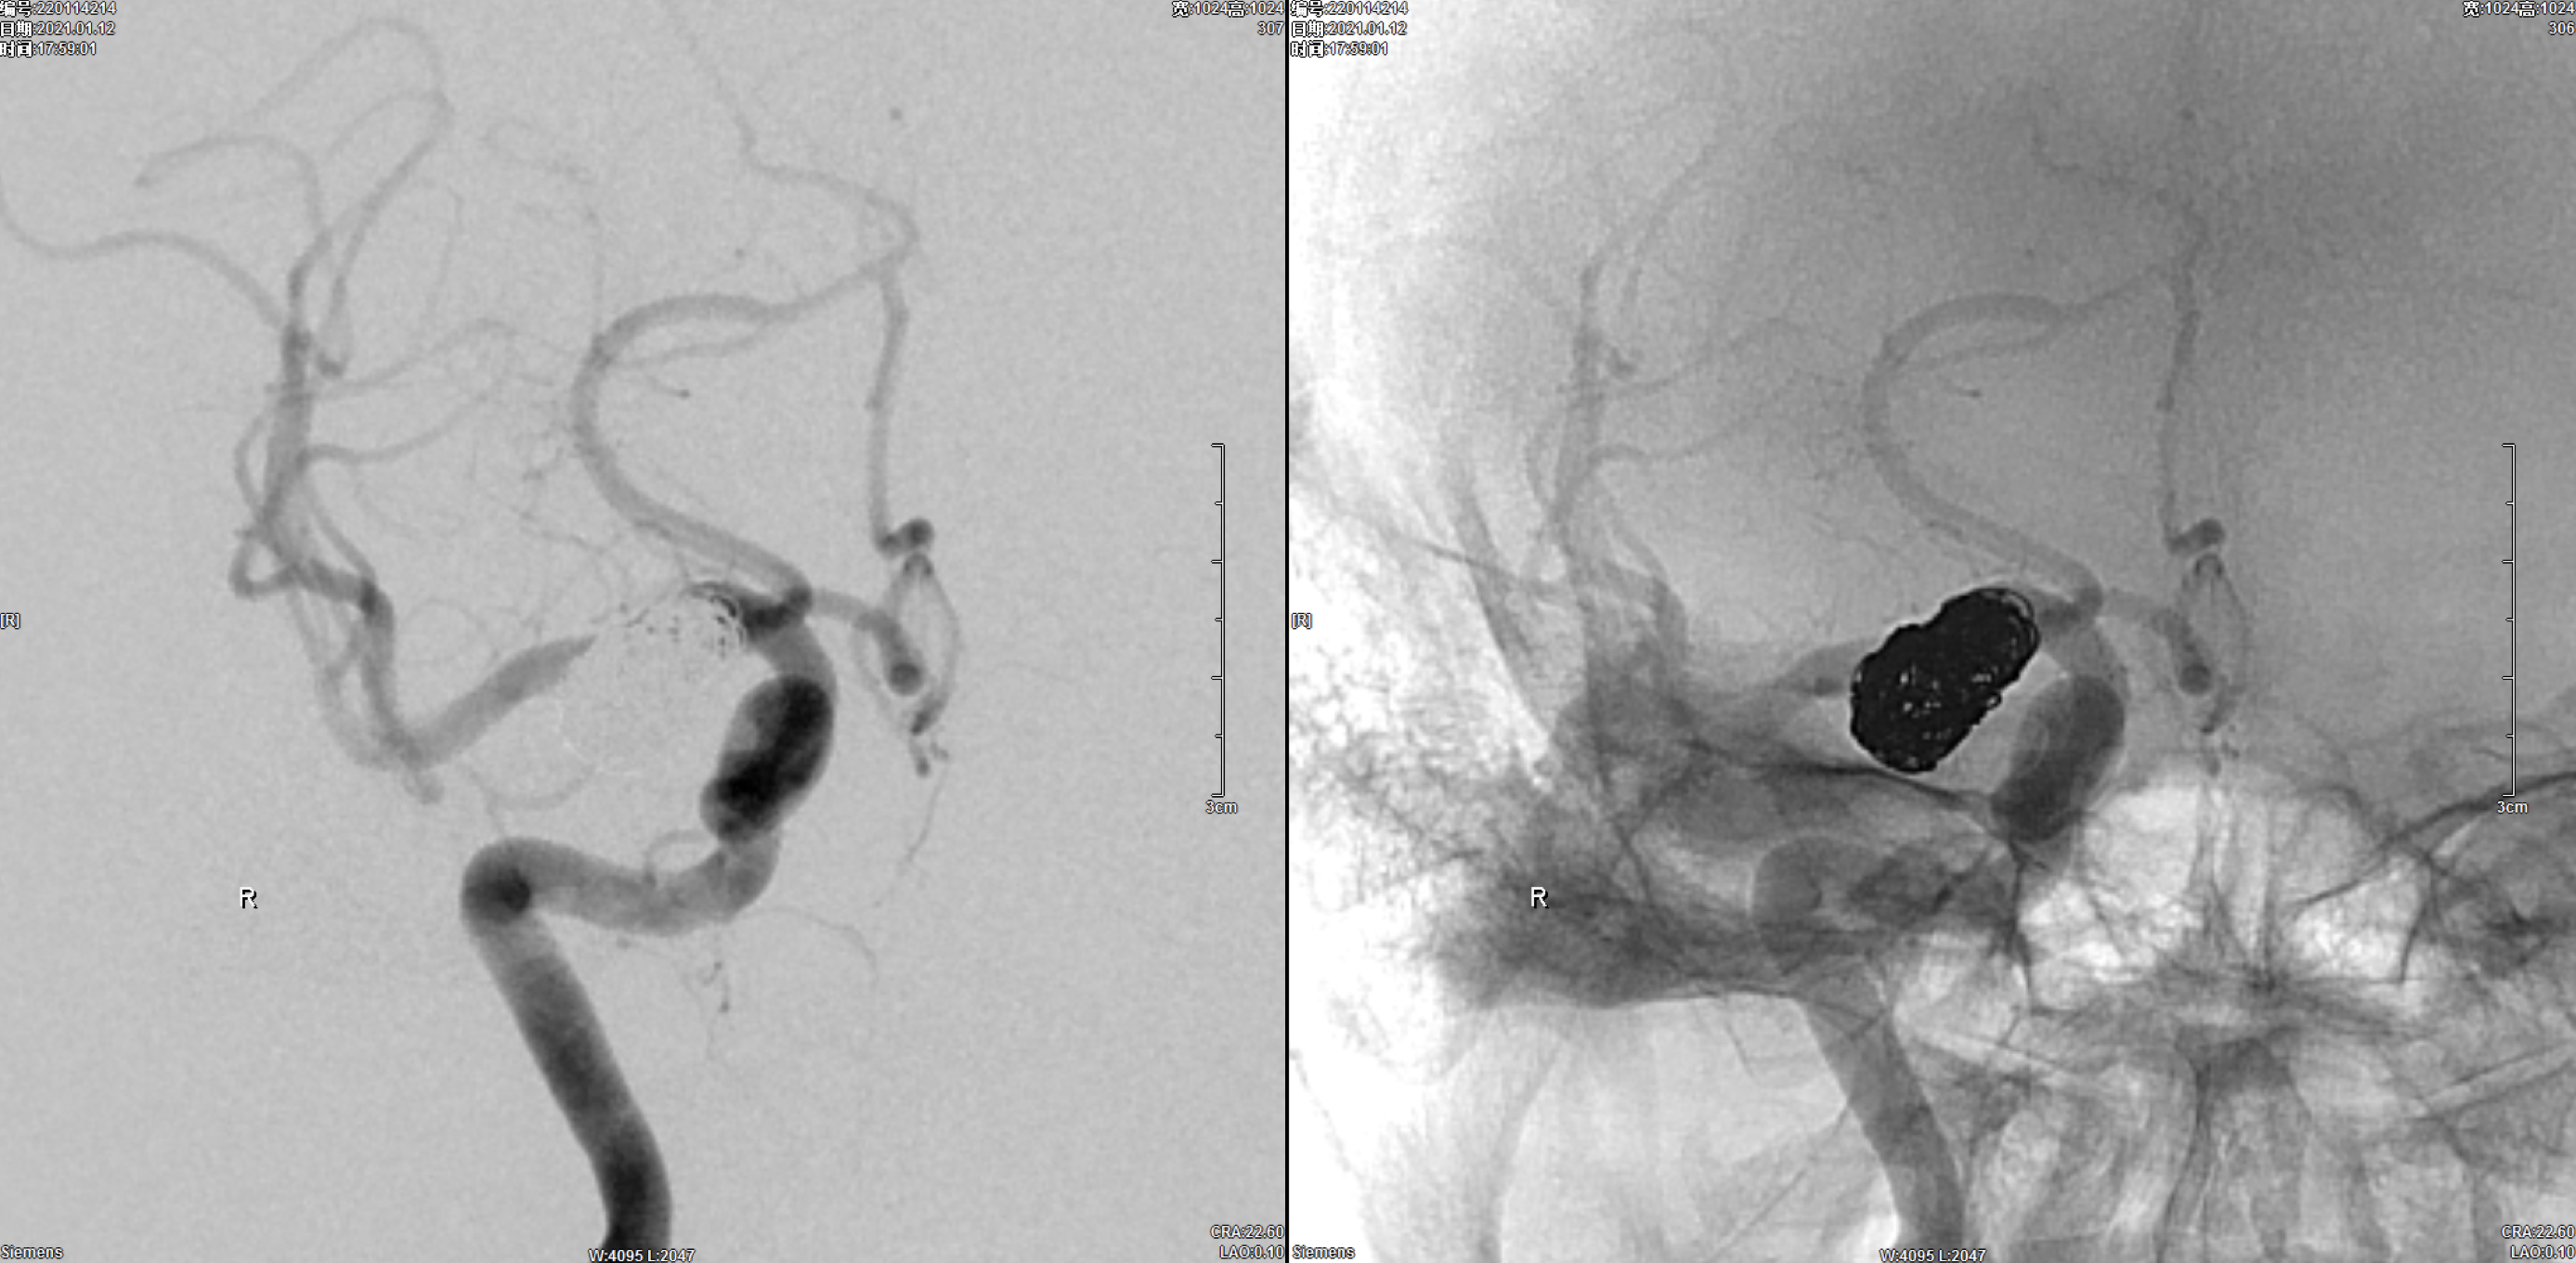

左侧颈内动脉正侧位造影:未见明显异常!

左侧颈动脉正侧位造影:未见明显异常!

右侧颈动脉正侧位造影:右椎动脉发育纤细!

右侧颈内动脉正侧位造影:后交通动脉瘤,后交通动脉发育粗大!